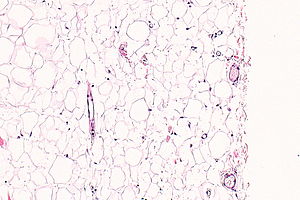

Mature adipose tissue (lipoma). H&E stain.

• Collection of mature adipocytes.

• Microscopically not definitely distinguishable from mature clump of fat.

The sections show mature adipocytes. There is no increase in vascularity. No thick fibrous septa are present.